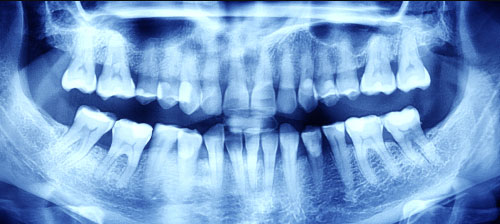

Dental X-rays can help your dentist to detect problems, like cavities, tooth decay, and impacted teeth. Book your dental x-ray appointment today with Lifeline Wisdom Dental.

- Dental X-rays are images of your teeth that your dentist uses to assess your oral health. Dental X-rays are done with very low levels of radiation to capture images of the inside of your mouth.

- Dental X-rays may seem complicated, but they are actually quite common and are just as important as your regular teeth cleanings. They provide your dentist with the most detail allowing them to correctly locate cavities, roots of the teeth, check overall oral health and view bone and tooth formation.

- Occlusal: This is done when your jaw is closed to see how the upper and bottom teeth match up. It can also detect any abnormalities with the floor of the mouth or the palate. This technique shows all of your teeth in one X-ray.

- Panoramic. This type of X-ray involves the machine rotating around your head. Your dentist may use this method to check your wisdom teeth or examine jaw problems.